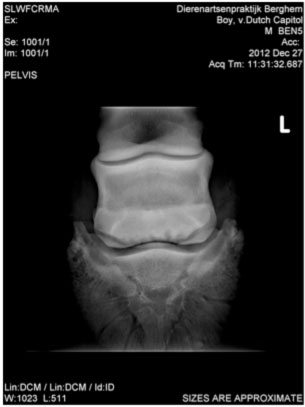

Example: 7-year-old Dutch Warmblood.

History: This horse was suffering from severe navicular disease as a 6-year-old, was extremely lame and was given up. As a last resort the horse was put on the Vitafloor twice daily initially and on improvement, reduced to treatment once a day.

Impressions: Photo on the right was taken 14 months after photo on the left. According to the veterinarian, the number of ‘lollipops’ has reduced (visible on originals on HD screen).